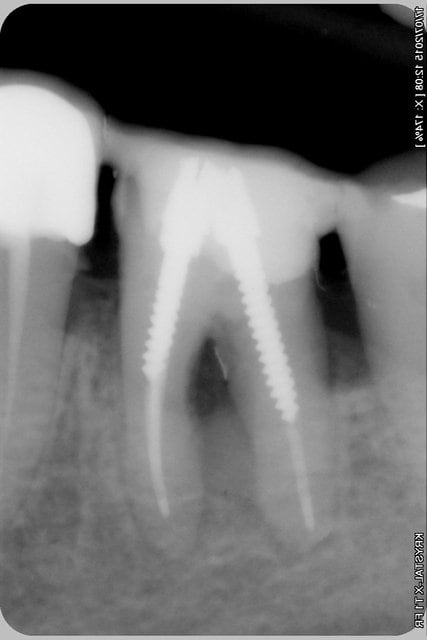

Tentative de sauvetage de 46, dépose de la ceramometal, et d'un magnifique inlay core à clavette (inter-radiculaire) (qui ne risquait pas de se barrer coincé entre les 3 parois restantes et un gros amalgame vestibulaire...(merci à la nomenclature qui rembourse ça...).

Nettoyage, curetage inter-radiculaires,lavage à l'hypochlorite, obturation (sans la digue) 3 screws post (en prévision d'une éventuelle séparation de racine)après avoir bouché la perforation à la bio dentine, recouverte d'un composite.

2 heures pour peut être rien, ou peut être pas?

sur les radios on distingue la biodentine sur la racine distale